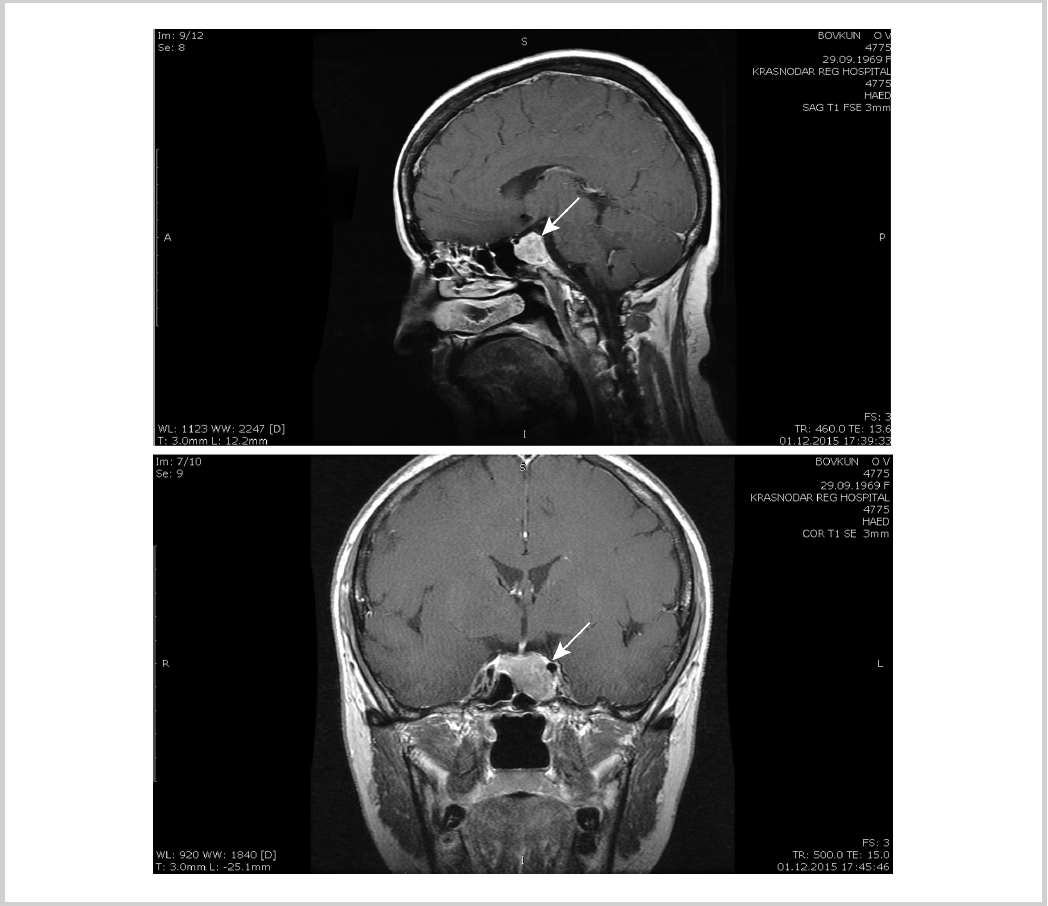

По данным МРТ гипофиза (01.12.15), объемное образование интра-, инфраселлярной локализации 17,7×27,1×19,5 мм, нижнелевые контуры массы расположены под левой внутренней сонной артерией. Воронка смещена вправо (см. рисунок).

Магнитно-резонансная томограмма головного мозга: макроаденома гипофиза.

На основании клинической картины заболевания, результатов гормонального исследования — повышенный уровень ТТГ, св.Т3, св.Т4 в отсутствие антител к рецептору ТТГ, своеобразные изменения тиреоидного статуса на фоне приема тиреостатиков [снижение св.Т3 до 5,74 пмоль/л с повышением ТТГ до 35,3 мкМЕ/мл и последующая при отмене тирозола нормализация уровня ТТГ (5,4мМЕ/мл) и наличие лабораторных признаков гипертиреоза (св.Т4 —21,47 пмоль/л, св.Т3 — 11,0 пмоль/л)], а также наличие макроаденомы гипофиза на МРТ — высказано предположение о тиреотоксикозе центрального генеза — ТТГ-секретирующей аденоме гипофиза. С целью уточнения диагноза и определения тактики лечения больная направлена в ФБУ «Эндокринологический научный центр» МЗ РФ (ЭНЦ).

На фоне терапии аналогами соматостатина пролонгированного действия был достигнут эутиреоз (март 2016 г.): ТТГ — 2,162 мМЕ/л, св.Т4 —15,35 пмоль/л, св.Т3 — 4,4 пмоль/л. Данных о смешанном характере секреции аденомы не получено (пролактин — 42 мЕд/л, ИРФ 1—122 нг/мл). При МРТ (01.12.15) подтверждена макроаденома гипофиза размером 20×27×18 мм с пара- и инфраселлярным распространением. Учитывая отказ пациентки от нейрохирургического лечения, а также высокую чувствительность к терапии аналогами соматостатина, рекомендовано продолжить консервативное лечение аналогами соматостатина пролонгированного действия с повторным рассмотрением показаний к хирургическому лечению через 6 мес. Из осложнений тиреотоксикоза выявлена начальная остеопения в лучевой кости (до –1,1 SD по Z-критерию) и гиповитаминоз D, в связи с чем назначены препараты витамина D. Выписана в удовлетворительном состоянии.